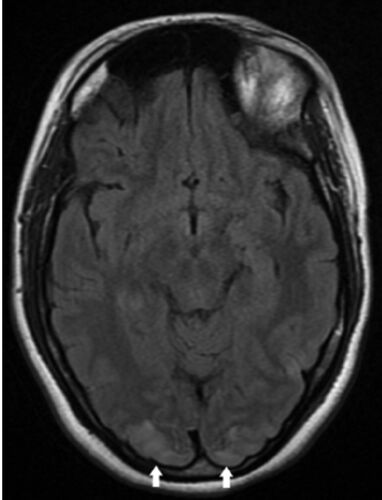

症例1:出産後に生じたけいれん発作(Ann Emerg Med. 2017 Jan;69(1):144-151.)

Annals of Emergenecy MedicineのImages in Emergency Medicineを1日1症例ずつ読んでいこうと思います。 これがもし1年続けば…すごい財産になるかも。 本日2020年11月10日を1日目として始めたいと思います! 病歴/身体所見 ・27歳女性 ・突然発症の頭痛/嘔吐…